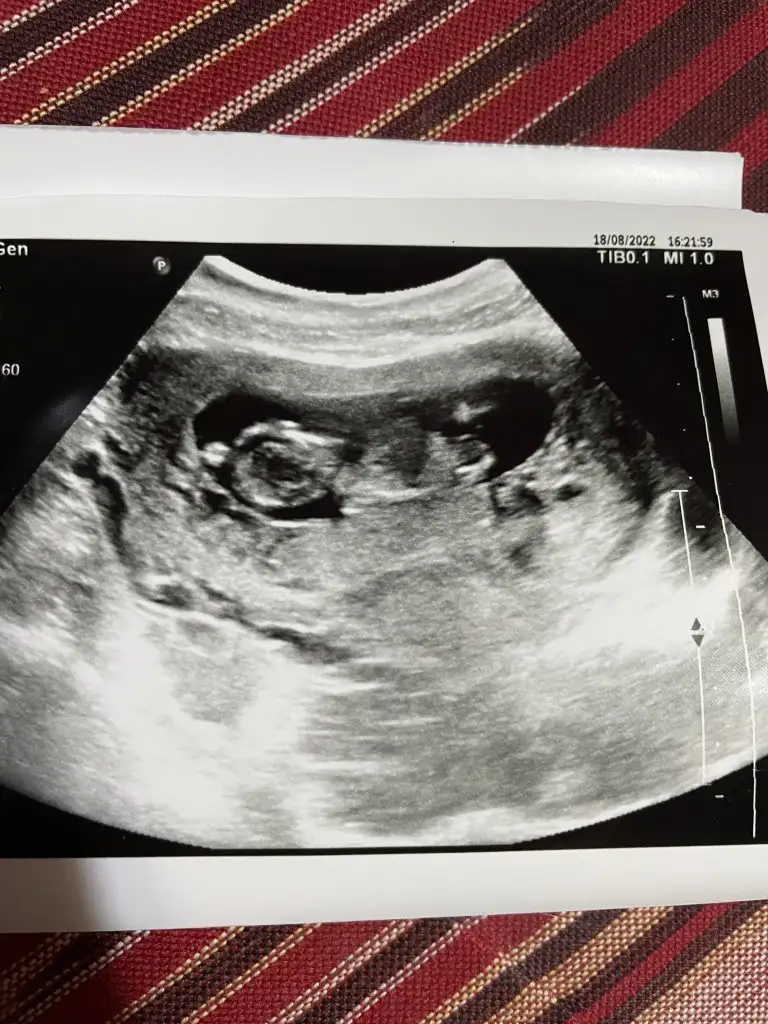

Merhabalar arkadaşlar ben yeni üyeyim sizden ricam ultrason resminden cinsiyet tahmini alabilirmiyim 12 hafta 6 günlük

Merhaba ben de yeni üyeyim, 12 haftalık hamileyim. Benim için de tahmin yapabilir misiniz rica etsem 🥰